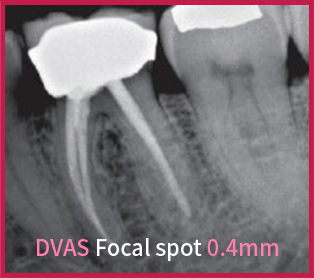

ЧЕТКОЕ ИЗОБРАЖЕНИЕ

Фокусное пятно размером 0,4 мм обеспечивает качественное изображение для стоматологов